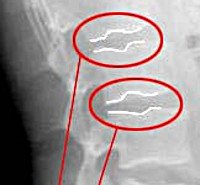

В диагностике основное значение имеют скудный характер жалоб или их отсутствие, наличие в анамнезе указаний на частое микротравмирование позвоночника, случаи выявления грыж у родственников пациента, искривление позвоночника или нарушение осанки, определяемые при визуальном осмотре пациента ортопедом, неврологом или вертебрологом. Достаточным методом инструментальной диагностики выступает рентгенография позвоночника. Зачастую она выполняется в связи с другой патологией, а грыжа Шморля является случайной диагностической находкой. Рентгенография позволяет выявить искривления позвоночника, наличие остеопороза, спондилоартроза, остеохондроза позвоночника.

Наличие в клинике выраженного болевого синдрома, не типичного для грыжи Шморля, указывает на возможное образование грыжи межпозвоночного диска. Поскольку последняя не визуализируется при помощи рентгенографии, в таких случаях показана МРТ позвоночника, а при невозможности ее проведения - КТ позвоночника.